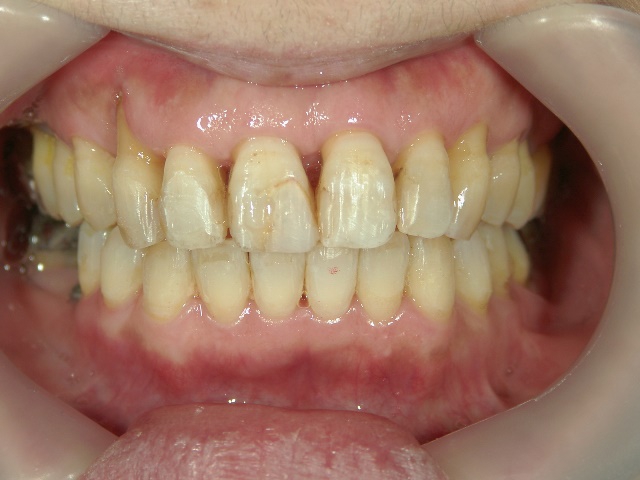

矯正歯科(全顎ワイヤー矯正)治療後

矯正歯科 治療後